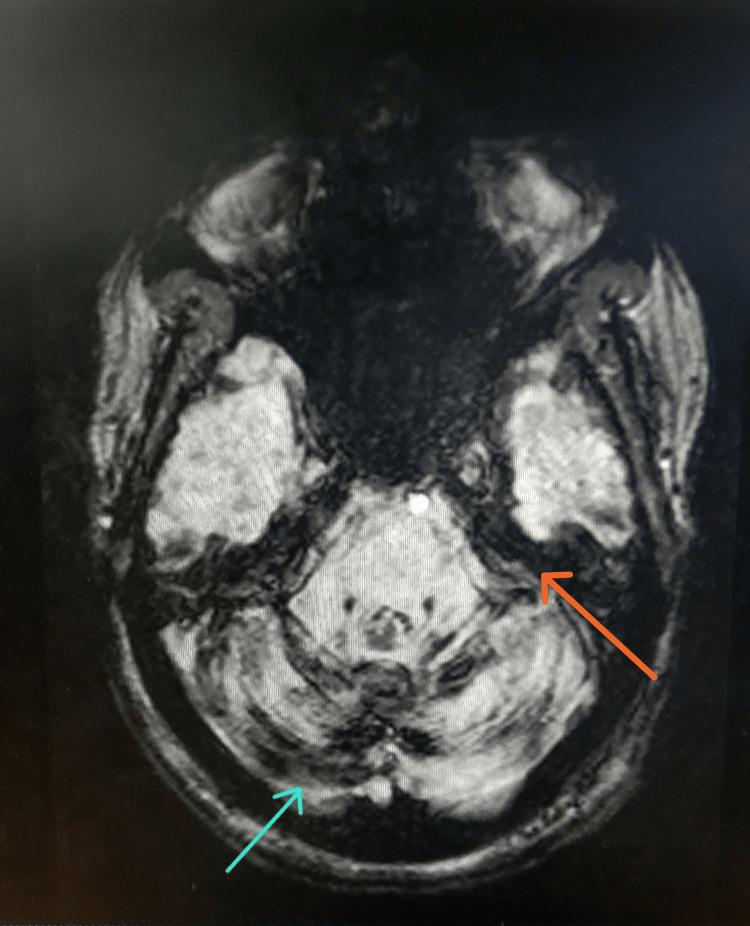

Superficial siderosis (SS) is a rare neurodegenerative condition caused by chronic or recurrent bleeding into the subarachnoid space, leading to the deposition of hemosiderin in the subpial layers of the brain, brainstem, spinal cord, or cranial nerves. SS is categorized into two main forms based on its anatomical distribution: cortical superficial siderosis (cSS) and infratentorial superficial siderosis (iSS). Among these, iSS is further subdivided into Type 1 (classical iSS) and Type 2 (secondary iSS). Classical iSS refers to cases in which there is no radiologically confirmed single spontaneous or traumatic intracranial hemorrhage and is typically associated with chronic bleeding sources, such as cranial or spinal dural defects. In contrast, secondary iSS is characterized by the presence of a radiologically identifiable single intracranial hemorrhagic event, either spontaneous or traumatic, which is considered the likely cause of the siderosis. Patients typically present with SS in the fourth to sixth decades of life. The prevalence of SS has been increasing in recent years due to the more widespread use of magnetic resonance imaging (MRI). Early imaging and diagnosis are crucial for identifying the bleeding source and enabling timely intervention, which may prevent further neurological deterioration. We report the case of a 69-year-old woman with a history of subdural hematoma and surgical intervention who presented with progressive bilateral hearing loss, imbalance, headache, and hypogeusia. MRI of the brain revealed classical imaging features of SS. Although further evaluation was recommended, the patient declined extensive diagnostic work-up. Empirical treatment with the iron-chelating agent deferiprone was initiated. This case highlights the diagnostic challenges of SS and emphasizes the importance of comprehensive imaging and early intervention.

浅表性铁沉积症(SS)是一种罕见的神经退行性疾病,由蛛网膜下腔慢性或反复出血引起,导致含铁血黄素在脑、脑干、脊髓或颅神经的软膜层沉积。根据其解剖分布,SS主要分为两种形式:皮质浅表性铁沉积症(cSS)和幕下浅表性铁沉积症(iSS)。其中,iSS又进一步细分为1型(经典iSS)和2型(继发性iSS)。经典iSS是指没有放射学证实的单一自发性或创伤性颅内出血的病例,通常与慢性出血源有关,如颅骨或脊髓硬脑膜缺损。相比之下,继发性iSS的特征是存在放射学可识别的单一颅内出血事件,无论是自发性还是创伤性,这被认为是铁沉积症的可能原因。患者通常在40至60岁出现SS症状。近年来,由于磁共振成像(MRI)的更广泛应用,SS的患病率一直在上升。早期成像和诊断对于确定出血源和及时进行干预至关重要,这可能会防止进一步的神经功能恶化。我们报告了一例69岁女性病例,该患者有硬膜下血肿病史并接受过手术干预,出现进行性双侧听力丧失、平衡失调、头痛和味觉减退。脑部MRI显示出SS的典型影像学特征。尽管建议进行进一步评估,但患者拒绝了广泛的诊断检查。开始使用铁螯合剂去铁酮进行经验性治疗。该病例突出了SS的诊断挑战,并强调了全面成像和早期干预的重要性。